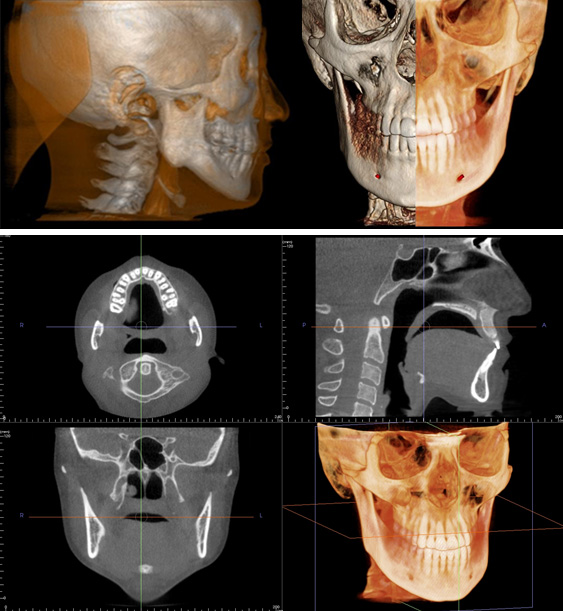

3Dデータ利用による、デジタル矯正治療システム

従来の矯正治療では、主に歯冠の並びを考慮して計画されていましたが、3Dデジタル矯正治療では、これまで把握できなかった歯根と歯槽骨の位置関係も含めて理想的な位置になるよう安全な治療計画が立案されます。

歯と歯根の CTスライス情報から、理想的な治療後の位置関係を決定していきます。

3Dデジタルデータから治療後の理想的な歯と歯根の位置をシュミレーション決定して、その場所に正確に歯と歯根が移動するようにロボットが極めて精密なワイヤーを作製します。このワイヤーの使用により、治療結果のクオリティが向上して、かつ治療期間が平均で25%減少するというデータが報告されています。

3D画像を用いてさらにわかりやすい説明

患者さんに安心して治療を受けていただけるように、3D画像を用いてさらにわかりやすい説明を行います。